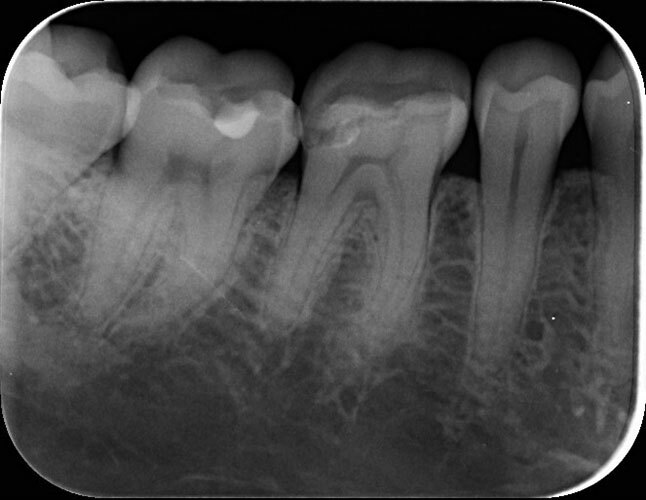

Dexis OP 3D Pro donosi potpuno digitalno rešenje za ortopantomogram (OPG), telediogram, skanogram, bitewing, i 3D snimke vilice, čime pruža sveobuhvatnu podršku dijagnostici za različite stomatološke zahvate i analize.

| Bitewing * | 1500 |